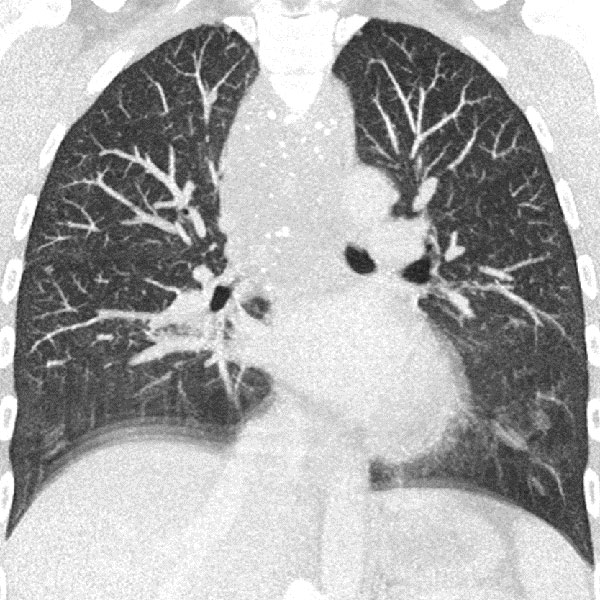

33-year-old female patient, since childhood recurrent attacks of "pseudocroup" with pronounced respiratory stridor. Previously known "hemangioma" of unclear origin in the neck. In an old thoracic CT, extensive mass in the neck, hypopharynx, larynx, down to the mediastinum. Multiple phleboliths in the mediastinum are clearly visible, indicating a venous malformation.

In connection with a systemic infection, now occlusion of the upper airway due to an inflammation-related increase in the swelling of the venous malformation; intubation became necessary. A biopsy was performed. On MRI in the coronal plane (T2-weighted, fat-suppressed), the lesion is very clearly visible as a strongly hyperintense mass. Extensive lesions in the hypopharynx and larynx on both sides.